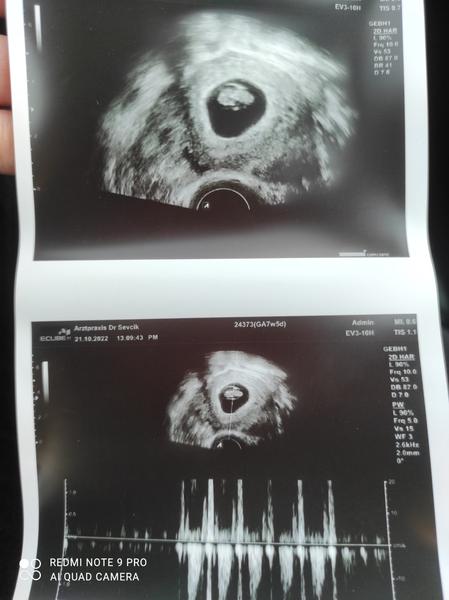

ahoj jsem v 5+3 a nejsem si moc jistá zda něco vidím a jak sem byla z toho tak nějak zaskočená na gynekologii tak sem se ani nezeptala co tam přesně vidí pan Doktor a aby mi to popsal , myslíte že je to takhle v pořádku?

Dutinka, v tomto týdnu normální. Zjistí se tak jedině, zda to není mimoděložní (to asi není, jinak by ti to řekl).